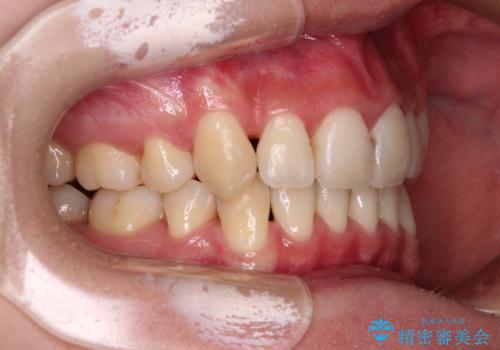

- 前歯の叢生と八重歯を気にして来院された患者様です。

叢生が強く、奥歯の咬合も左右差が大きかったため、上下左右4本を抜歯して、ワイヤー矯正を行うこととしました。

20歳前後と年齢が若かったため、非常にスムーズに歯列が整い、1年半をかけずに治療を終えることができました。